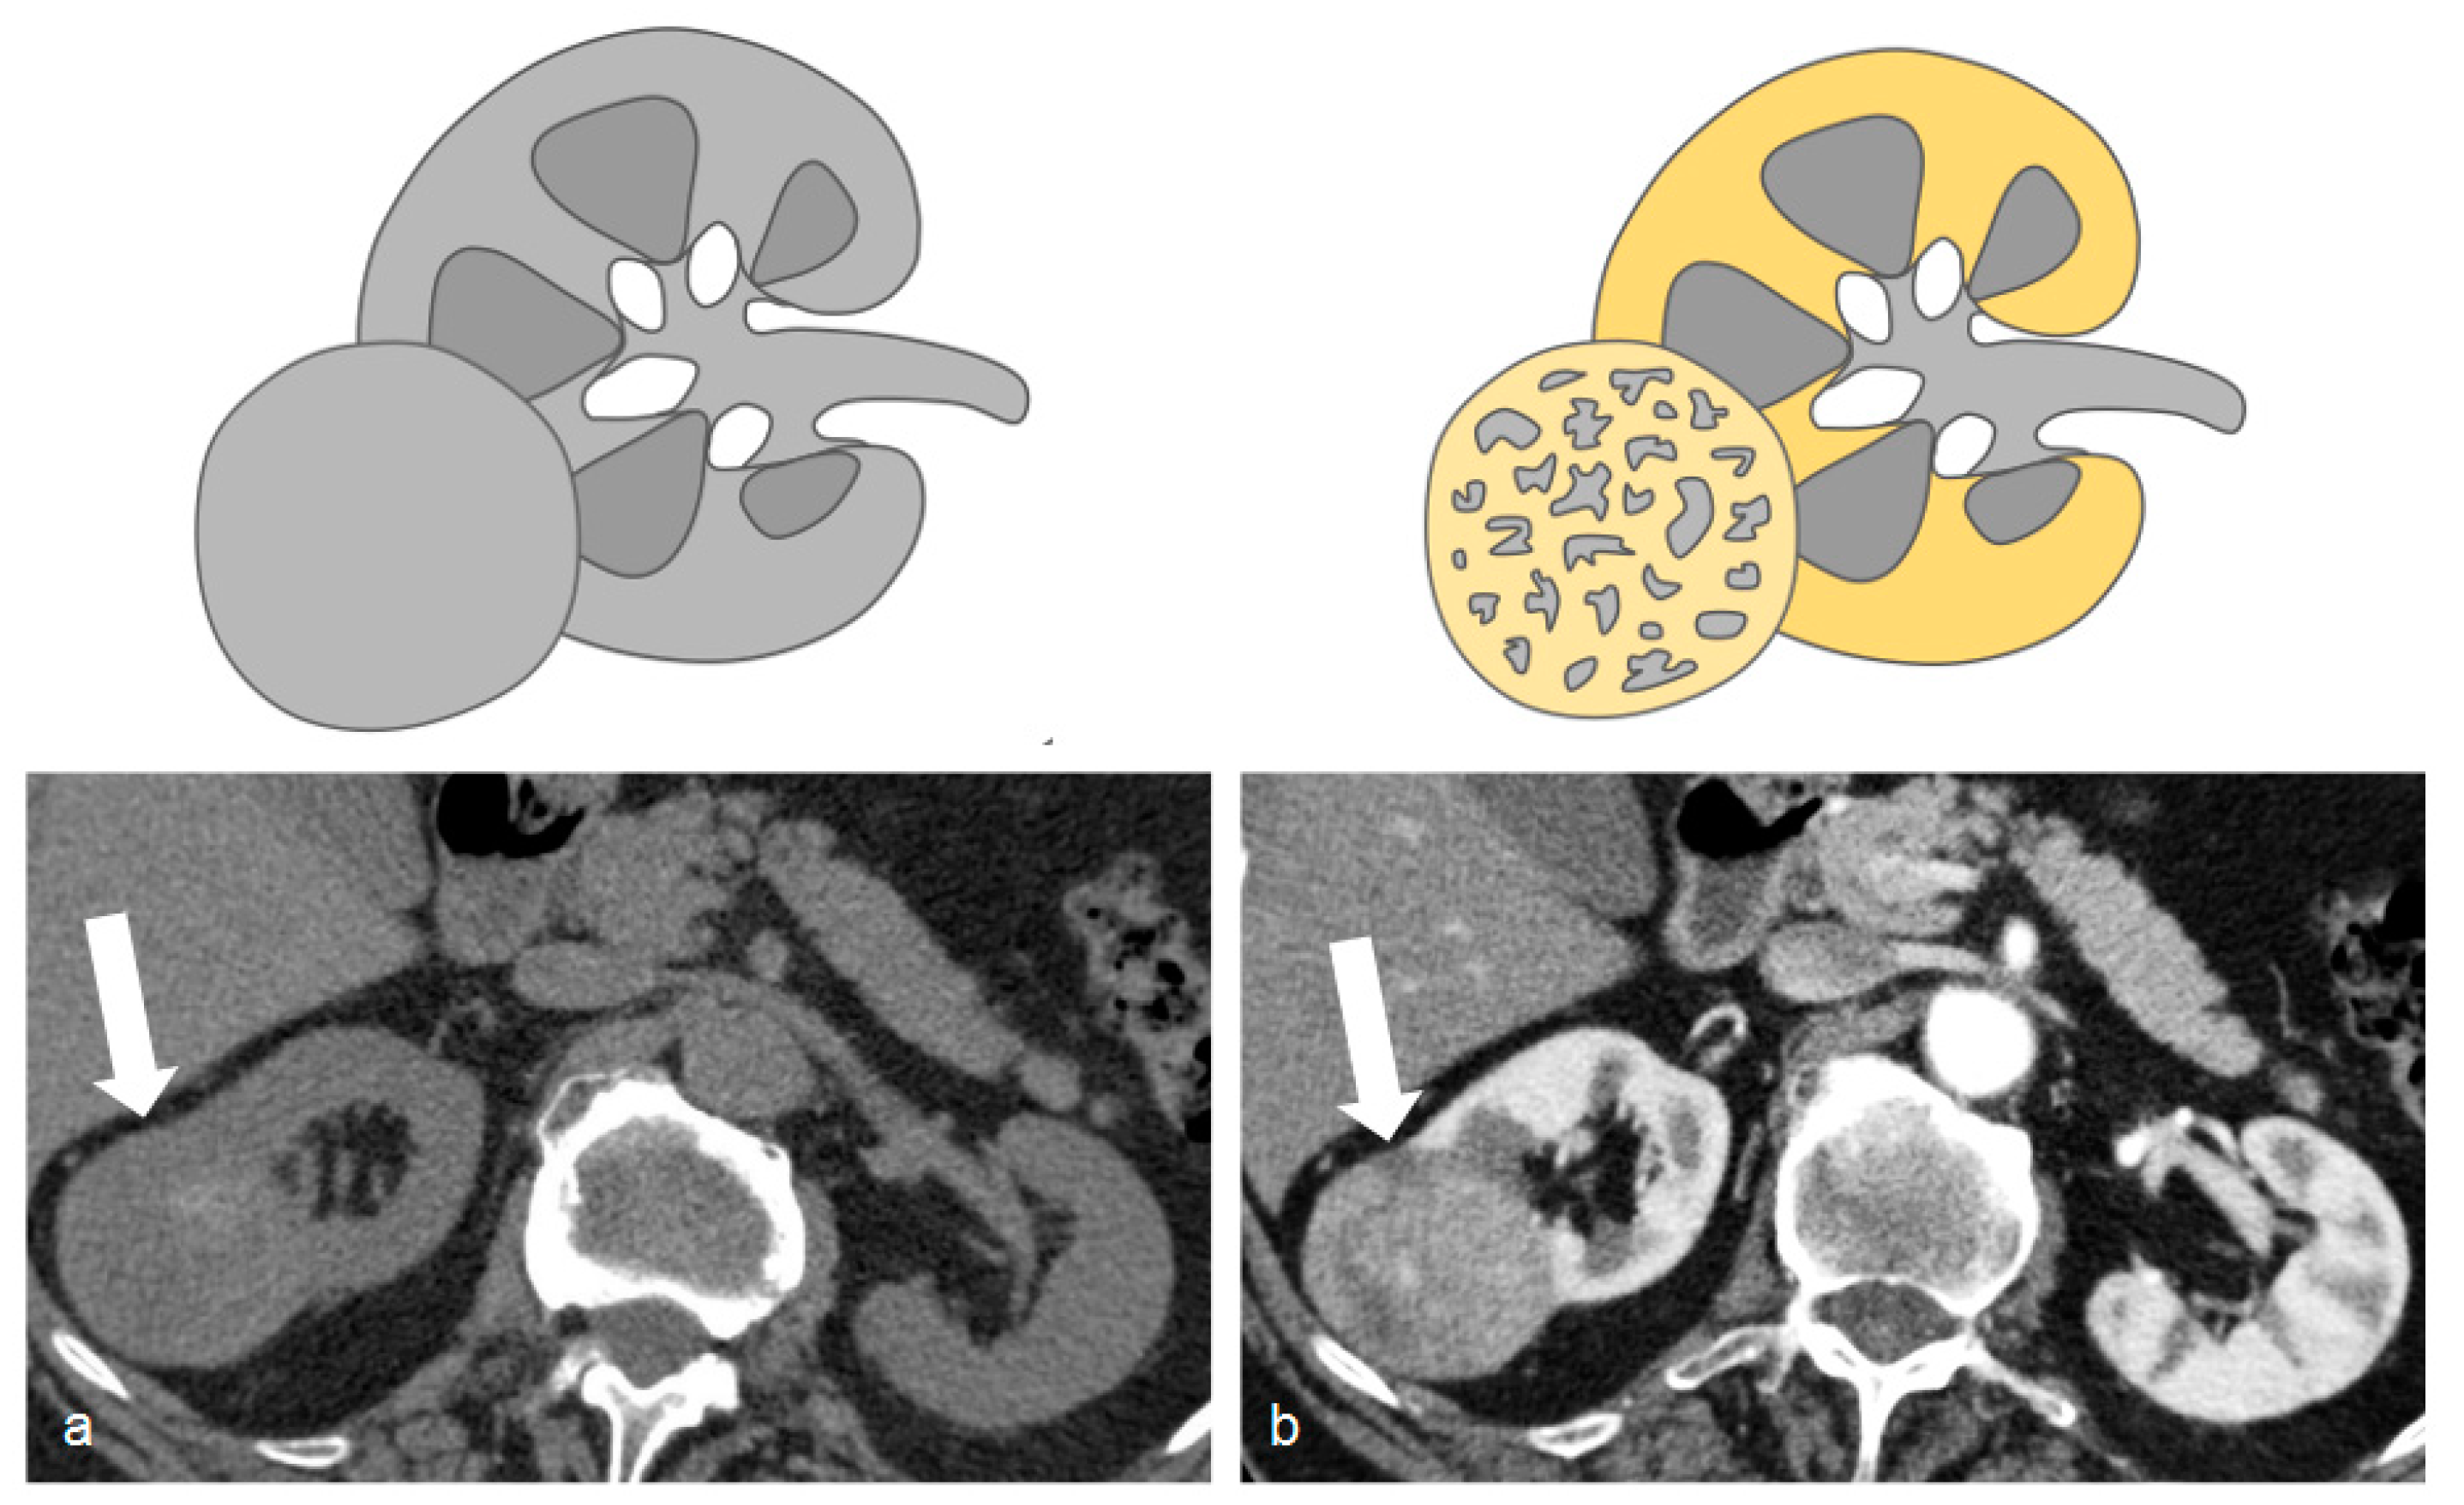

DECT images can also be post-processed to create maps that show the concentration of different components including iodine, fat, and calcium. The construction of iodine maps aids in the identification of tissues with higher or lower iodine concentrations (Figure 10, Figure 11 and Figure 12).

Figure 10.

(a) Dual-energy acquisition of a corticomedullary phase with visualization of the iodine map. (b) The posterior and external renal components do not show iodine contents, whereas the anterior nodulation shows clear iodine content.

Iodine density measurements have different applications. First, they enable the management of incidentally detected renal masses, allowing their characterization from a single examination and avoiding additional imaging and diagnostic timing delays [73]. Virtual monochromatic images demonstrated better correction of beam hardening artifacts, reducing the degree of pseudo-enhancement in intraparenchymal renal cysts, and allowing for a more confident diagnosis, when compared to standard CT acquisitions [74].

Iodine density measurements and iodine overlay images provide a visual depiction of enhancement that helps in the discrimination between avidly enhancing clear cell renal cell carcinoma and hypoenhancing papillary renal cell carcinoma [75] and is also particularly useful in the assessment of treatment response when using targeted antiangiogenic agents for clear cell renal cell carcinoma [76] and in patients treated with ablation [77].